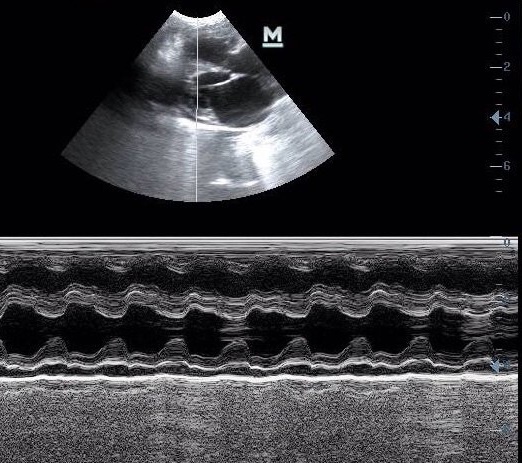

Диагностирование и своевременное лечение ГКМП – это важное условие для того, чтобы уменьшить тяжесть клинических симптомов и снизить вероятность возникновения тромбов. Лучше всего ГКМП диагностируется с помощью эхокардиографии – технология, которая использует звуковые волны для создания изображения сердца. Электрокардиограмма может быть полезной, чтобы охарактеризовать частоту сердечных сокращений и исключить нарушения ритма сердца. Рентгенография также может быть полезной для оценки состояния легких и исключить плеврит.